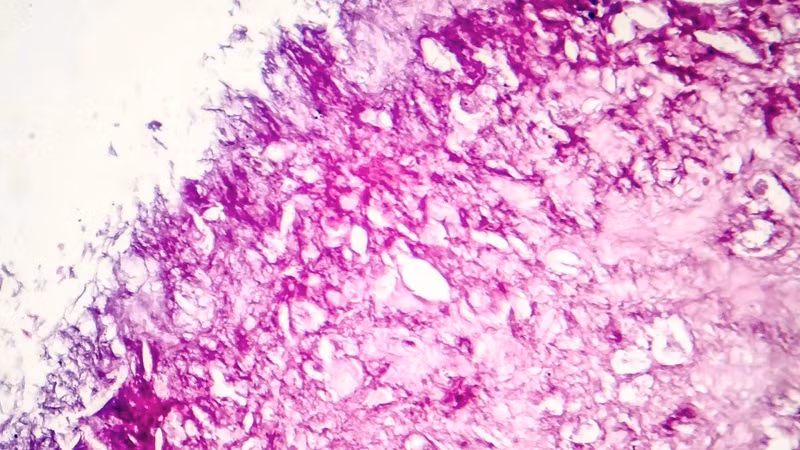

Một ví dụ về các tế bào khối u ác tính. (Ảnh: Canva)